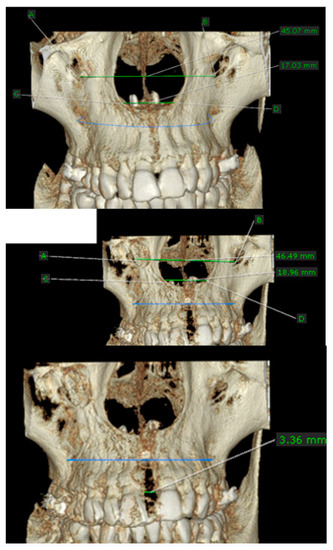

| Parameter | Interincisal Opening at the CEJ Level/Millimeter |

|---|---|

| Minimum | 3.360 |

| 25% percentile | 3.783 |

| Median | 4.210 |

| 75% percentile | 4.365 |

| Maximum | 4.770 |

| Mean | 4.103 |

| SD | 0.3881 |

| SEM | 0.08679 |

| Lower 95% CI of mean | 3.921 |

| Upper 95% CI of mean | 4.284 |

| Anterior Nasal Spine (ANS) Opening after Treatment | Posterior Nasal Spine (PNS) Opening after Treatment | |

|---|---|---|

| Number of values | 20 | 20 |

| Minimum | 2.970 | 2.670 |

| 25% Percentile | 3.250 | 2.780 |

| Median | 3.900 | 2.995 |

| 75% Percentile | 4.165 | 3.385 |

| Maximum | 4.540 | 4.110 |

| Mean | 3.766 | 3.125 |

| SD | 0.4956 | 0.4070 |

| Standard error of mean (SEM) | 0.1108 | 0.09102 |

| Lower 95% CI of mean | 3.534 | 2.934 |

| Upper 95% CI of mean | 3.998 | 3.316 |